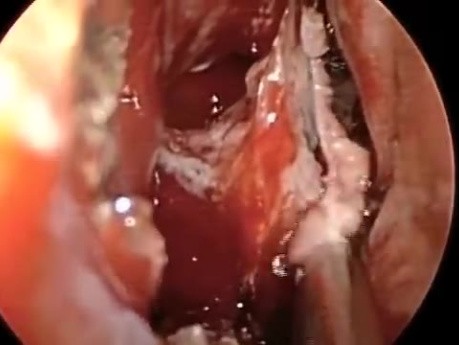

Endoskopowa operacja przysadki - wykorzystanie...

Wideo przedstawia przeznosowy i przezklinowy dostęp do przysadki w celu wykonania operacji siodła. Wykorzystano endoskop kątowy.